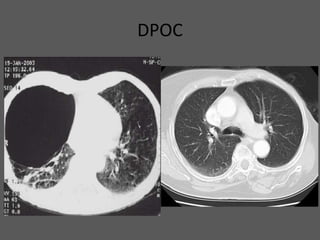

DPOC